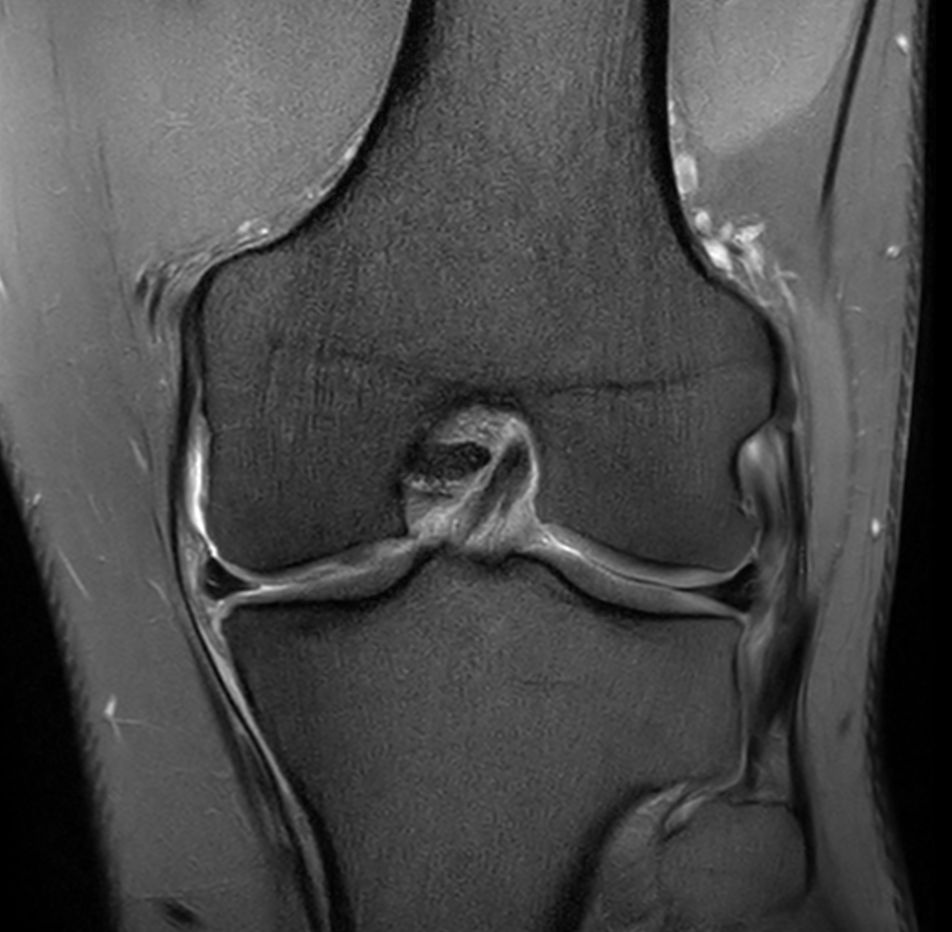

Coronal PDw SPIR - Compressed SENSE